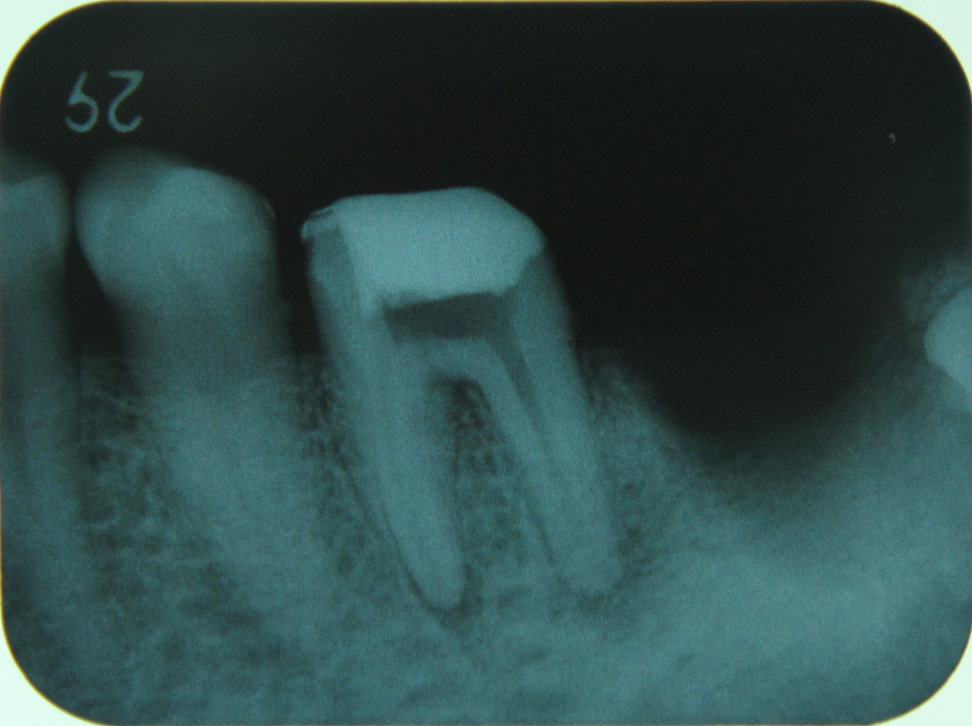

![]()

レントゲンで虫歯の大きさや歯髄の大きさ、位置を確認します